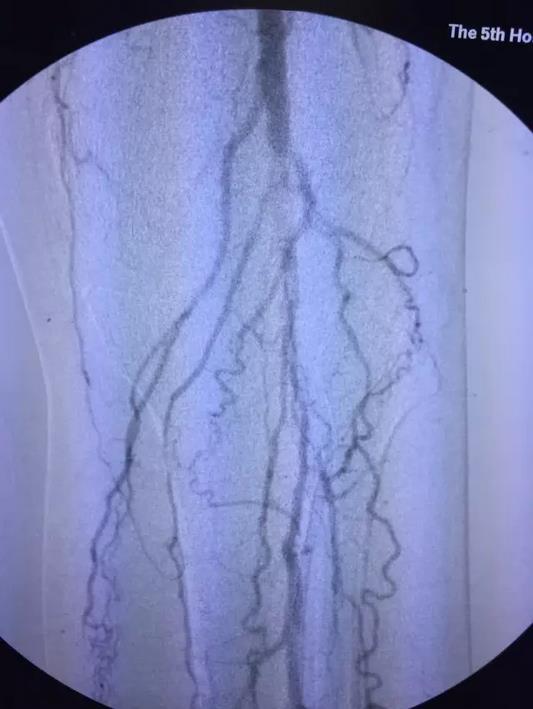

术后因患者长时间留置动脉鞘管,易导致菌血症、鞘管内血栓形成等并发症。施敏护士长带领的护理团队术后严格无菌操作,按时冲洗鞘管,避免了上述并发症的发生。5天后复查造影(图3,4,5,6,7):腹主动脉,左侧髂动脉,股动脉全程通常,膕动脉短段闭塞,但周围侧枝血管丰富,可较好的代偿至膝下。患者左下肢的皮肤温度和颜色明显改善,下肢疼痛,发凉等缺血症状缓解,出院前复查CTA效果良好(图8)。

图7 溶栓后膝下动脉造影